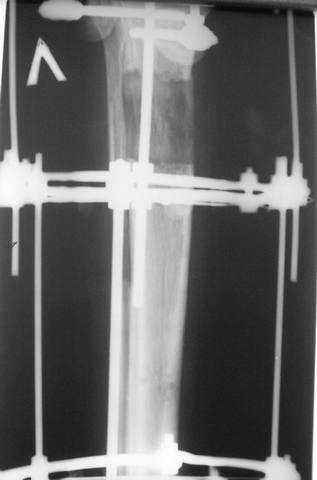

5. Ну и чтобы не быть голословным. Молодой человек подорвался на фугасе (Чечня, 2005 год). Свежие рентгенограммы:

Соответственно ожоги и дефект мягких тканей, переломы костей стопы и пр. Наложили аппарат

Илизарова (как придется), хирургически обработали и героически заживляли мягкие ткани с многочисленными кожными пластиками. В итоге через полгода я принял его вот таким:

Реализовал описанную выше методику, и в итоге вот что получилось. Высылаю лишь прямые проекции,

в боковых тоже всё в тему.

Очень пригодились карбоновые кольца (Джолдас -огромное спасибо, я твой должник!!!), поскольку остеопороз дистального отломка был просто невероятный. На цифровом рентгене с трудом угадывались контуры.

Рентген в процессе перемещения - внизу карбоновые кольца, тракция фрагмента спицами с упором.

внешний вид в аппарате - не завершающем этапе, сначала стопа тоже была фиксирована в аппарате.

Сейчас аппарат сняли, но случай ещё не завершенный.

Признаюсь честно, не совсем уверен в прочности консолидации на стыке косточек. Кроме того, укорочение в районе 6 см. Сейчас реабилитация - ходит опираясь на ногу с одним костылем.

Продолжение, видимо, будет... Возможно, будем удлинять.